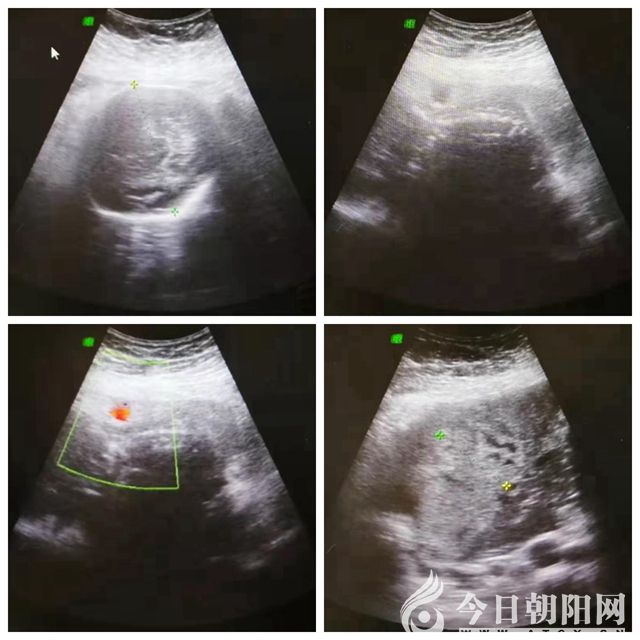

8月7日下午4時10分,家住朝陽市雙塔區(qū)的王女士因“停經(jīng)7個月、不規(guī)律腹痛1天”來到市二院就醫(yī)。外地超聲懷疑腹腔妊娠,乘車從錦州返回朝陽就診。產(chǎn)科一病房接診醫(yī)生詢問病情后,立即匯報科主任,科主任緊急請示院領(lǐng)導。王憲珍副院長得知情況后,迅速組織婦產(chǎn)科主任孫鳳華、產(chǎn)科一病房主任白麗萍、超聲科主任張華杰等人員到超聲科進行全院會診,簡單詢問病史及查體后當即診斷為:妊娠30周零6天、瘢痕子宮、子宮破裂。由于病情危重,腹腔內(nèi)多量積血,目前胎兒尚存活,需即刻手術(shù),否則將危及母嬰兩條生命。在此緊急情況下,醫(yī)院立即開通綠色通道,啟動危重孕產(chǎn)婦搶救預案,通知檢驗科、手術(shù)室、輸血科、麻醉科、新生兒科等科室迅速做好術(shù)前準備,短短數(shù)分鐘就把患者從超聲科直接推入手術(shù)室。

在全麻下,迅速開腹腔,術(shù)中見盆腹腔積血及血塊約1500毫升,胎兒此時游離于大量血液之中,快速于腹腔中取出一女活嬰,新生兒輕度窒息,斷臍后交臺下處置。探查見患者子宮右側(cè)宮角增大約15x10厘米,表面紫藍色,見破裂口長約6厘米,多量活動性出血,整個胎盤植入于右側(cè)宮角,向患者家屬交代病情,行部分子宮切除術(shù)及子宮成形術(shù)。術(shù)中輸紅細胞4單位、血漿400毫升。一切都在緊張有序中進行,此時的手術(shù)室就像一個沒有硝煙的戰(zhàn)場,大家鼓足了勁,拼命和死神賽跑。